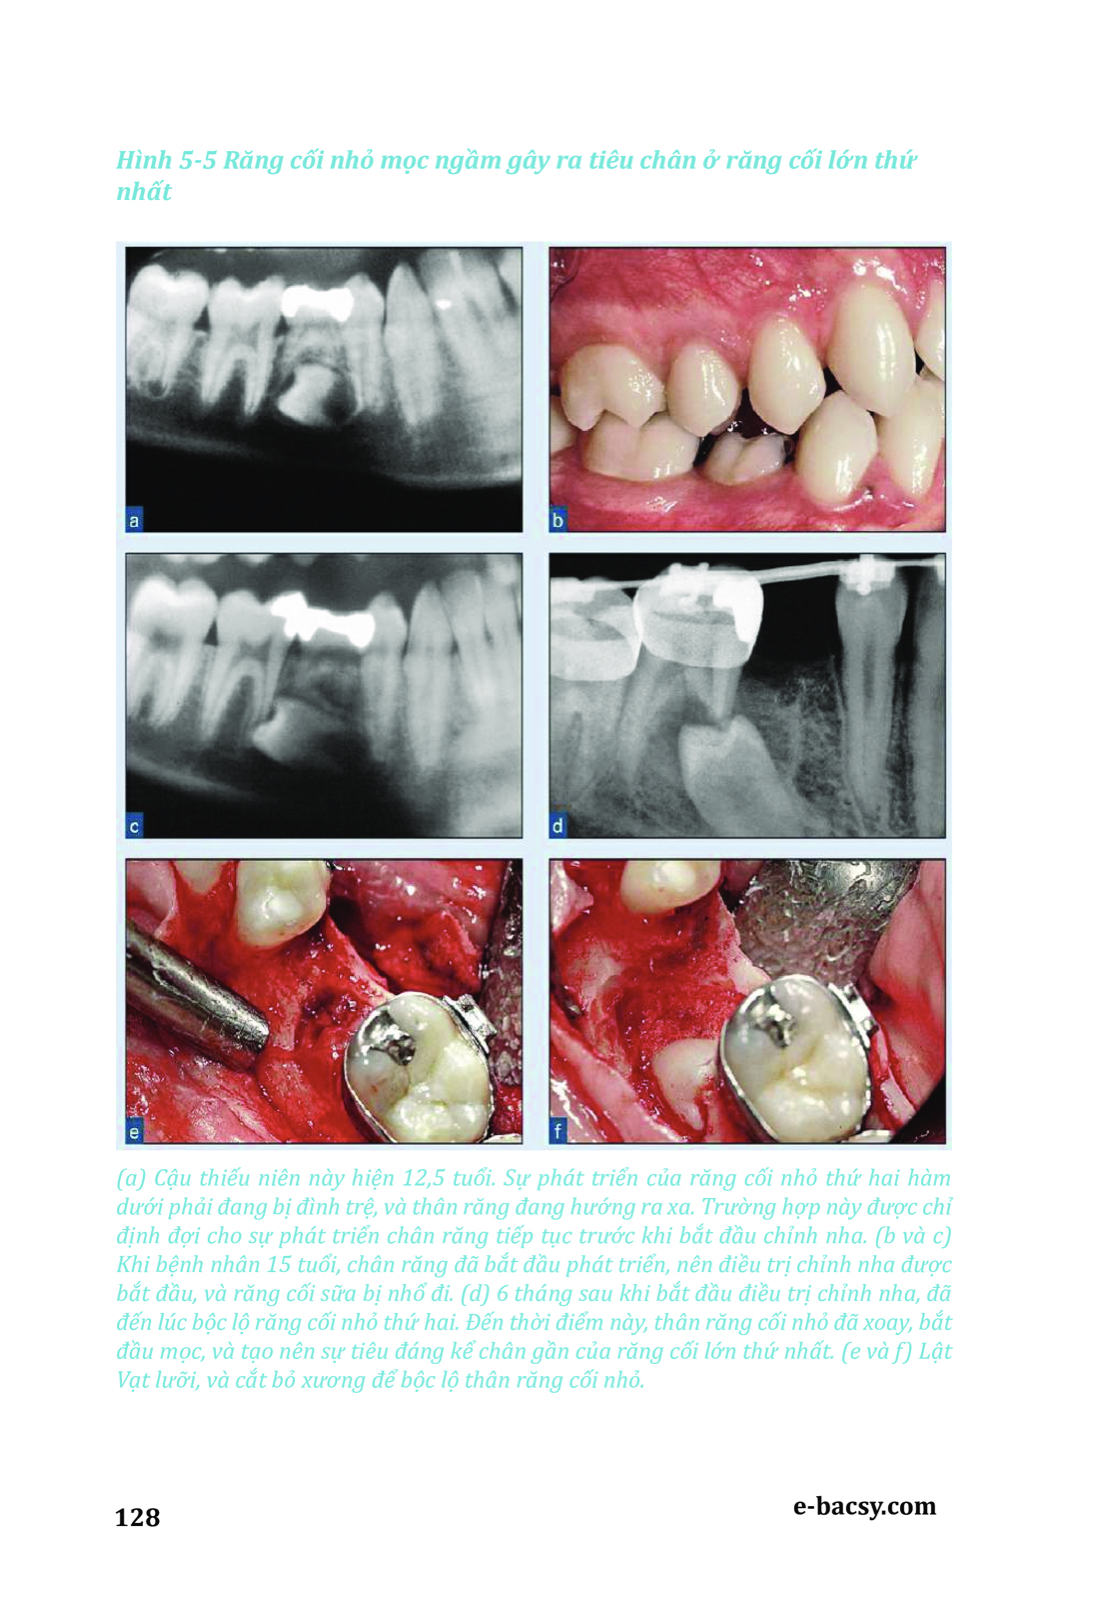

Răng mọc ngầm - Phẫu thuật cùng chỉnh nha